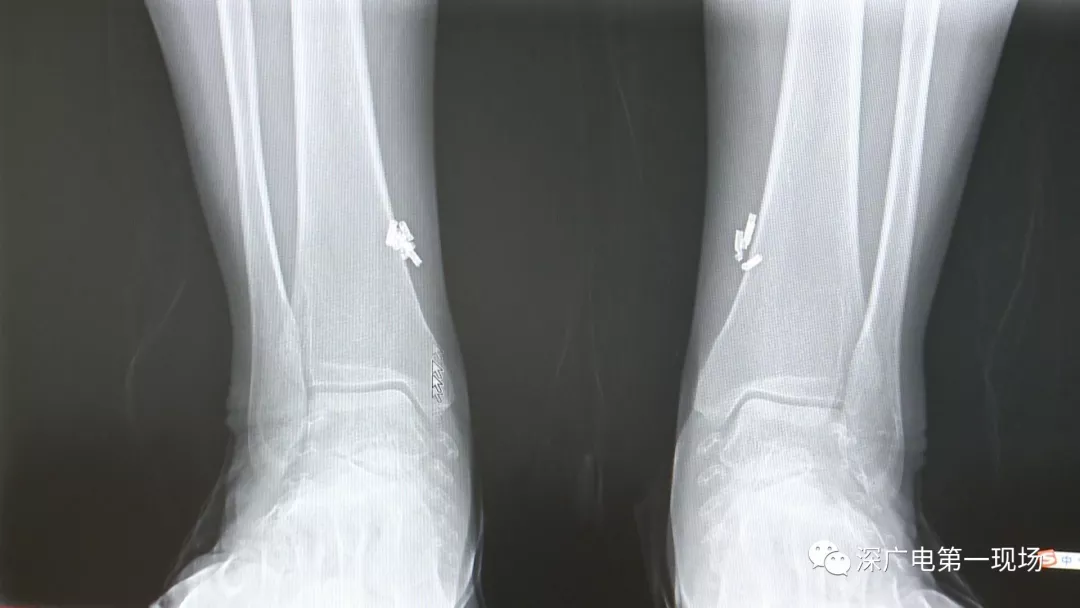

從X光影像圖片中可以看到

患者周身布滿了彈簧圈

深圳大學(xué)總醫(yī)院神經(jīng)外科副主任醫(yī)師陳富勇介紹,當時檢查的時候發(fā)現(xiàn),該患者從頭部到腿部,基本上每個地方都有彈簧,很難數(shù)清具體數(shù)目。